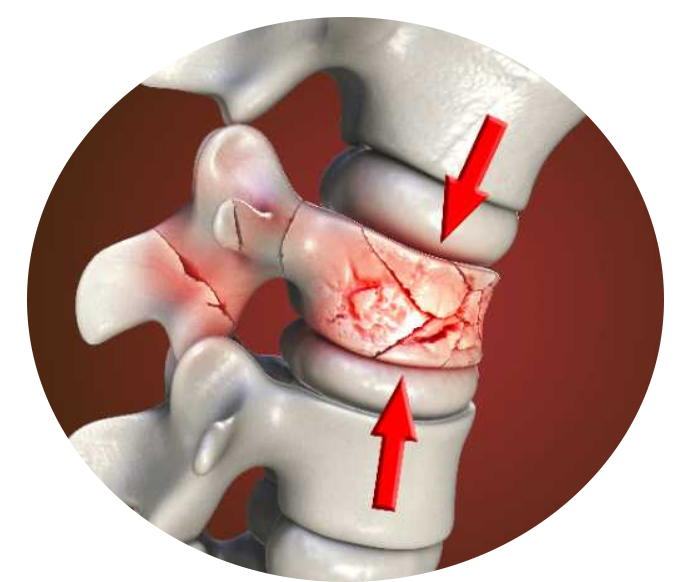

Você sente dores na coluna, formigamentos, dormências e diminuição de força nos braços e pernas? A dor na coluna não d eve ser encarada como uma inimiga, mas sim como um mecanismo de proteção do nosso corpo, agindo para evitar danos maiores. No entanto, quando essa dor persiste além do necessário, mesmo após a causa inicial ter desaparecido, é aí que surgem os problemas.

Consideramos a dor na coluna como crônica quando persiste por pelo menos três meses, e quando passa a interferir significativamente na rotina diária do paciente, afetando sua qualidade de vida e produtividade.

Para lidar com a dor crônica na coluna, é essencial adotar uma abordagem abrangente, que inclua técnicas cirúrgicas avançadas, intervenções minimamente invasivas e uma equipe multidisciplinar dedicada ao manejo da dor. Aliviando a dor crônica na coluna, não apenas melhoramos a função física, mas também elevamos a qualidade de vida dos pacientes.